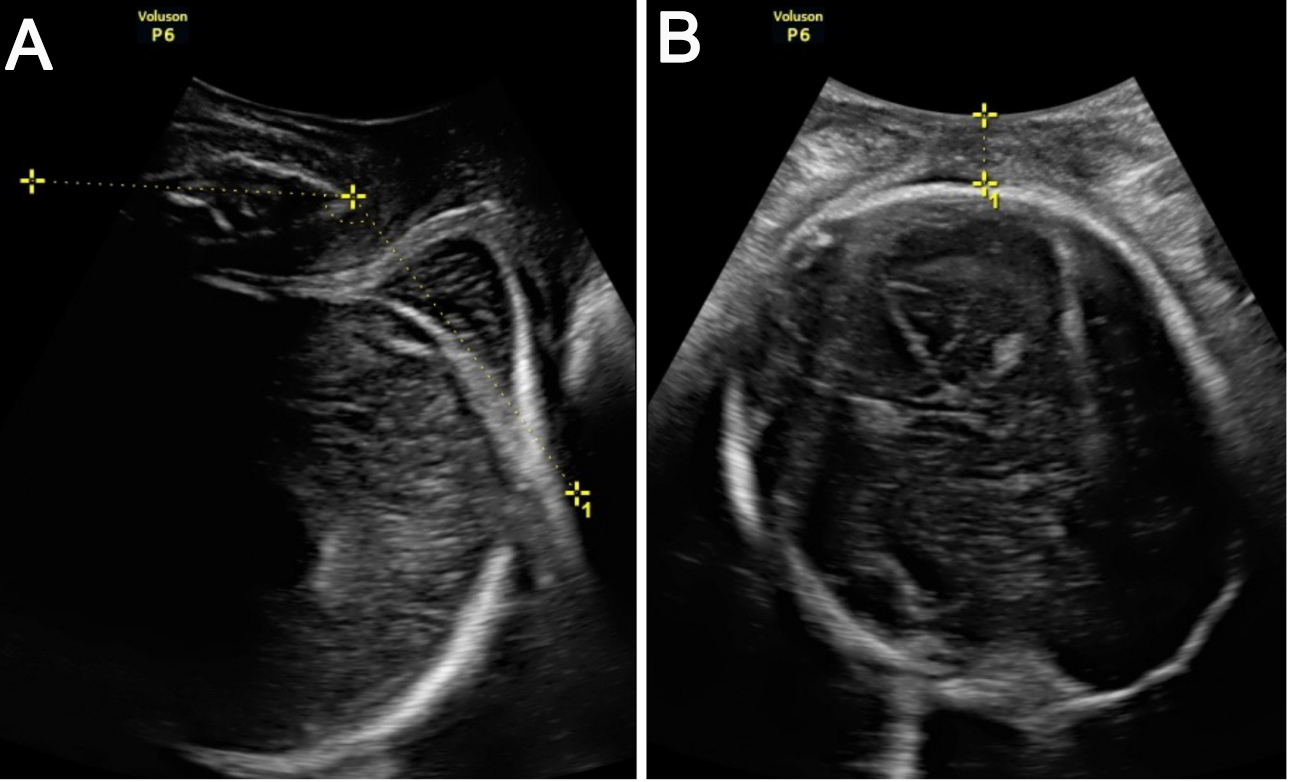

To perform the ITU, the women were asked to grasp their upper knee and flex it (Fig. 1). The transducer was first placed in the frontal plane and then rotated to the midsagittal plane (the probe was placed at the level of the fourchette).

Fig. 1.Maternal lateral position and placement of the probe. (A) Transducer placed in the frontal plane. (B) Transducer placed in the midsagittal plane.